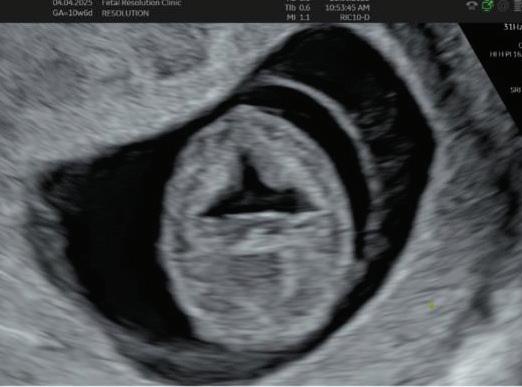

The first trimester— spanning from conception to 13+6 weeks—is no longer considered a “blind phase” of pregnancy. With the evolution of highresolution ultrasound, color Doppler and advanced biochemical screening, this period has transformed into a window of opportunity for early fetal evaluation, risk prediction and preventive strategies.

First-trimester fetal evaluation is not limited to dating the pregnancy or confirming viability—it is the foundation of predictive, preventive, and personalized obstetric care.

2. NUCHAL TRANSLUCENCY (NT) SCAN

• Done @11–13+6 weeks.

• CRL 45–84 mm.

• This is the cornerstone of first trimester screening.

1. NT is the sonographic appearance of subcutaneous accumulation of fluid behind the fetal neck, below the skin in the first trimester of pregnancy.

2. Measured in mid-saggital section only.

3. Measured between 11-14 weeks.

4. CRL between 45-84mm.

5. Magnified to include only head and upper thorax.

6. Fetus should be in neutral position.

7. Demostrate fetus separate from amnion.

8. Measurement should be ON to ON (cross bar of the callipers should be such that it’s hardly visible and merges with white line, not nuchal fluid).

During the scan more than one measurement should be taken and maximum value should be considered.

NASAL BONE:

Hypoplasia defined as length <2.5mm.

Absent METHOD OF MEASUREMENT

• Mid saggital plane.

• Good face profile.

• At 45 degree angle with imaginary line from forehead to chin.

• 3 echogenic lines.

• Absent nasal bone is more common if The gestation is 11 than 13 weeks. The fetal nuchal translucency is high. The mother is Black.